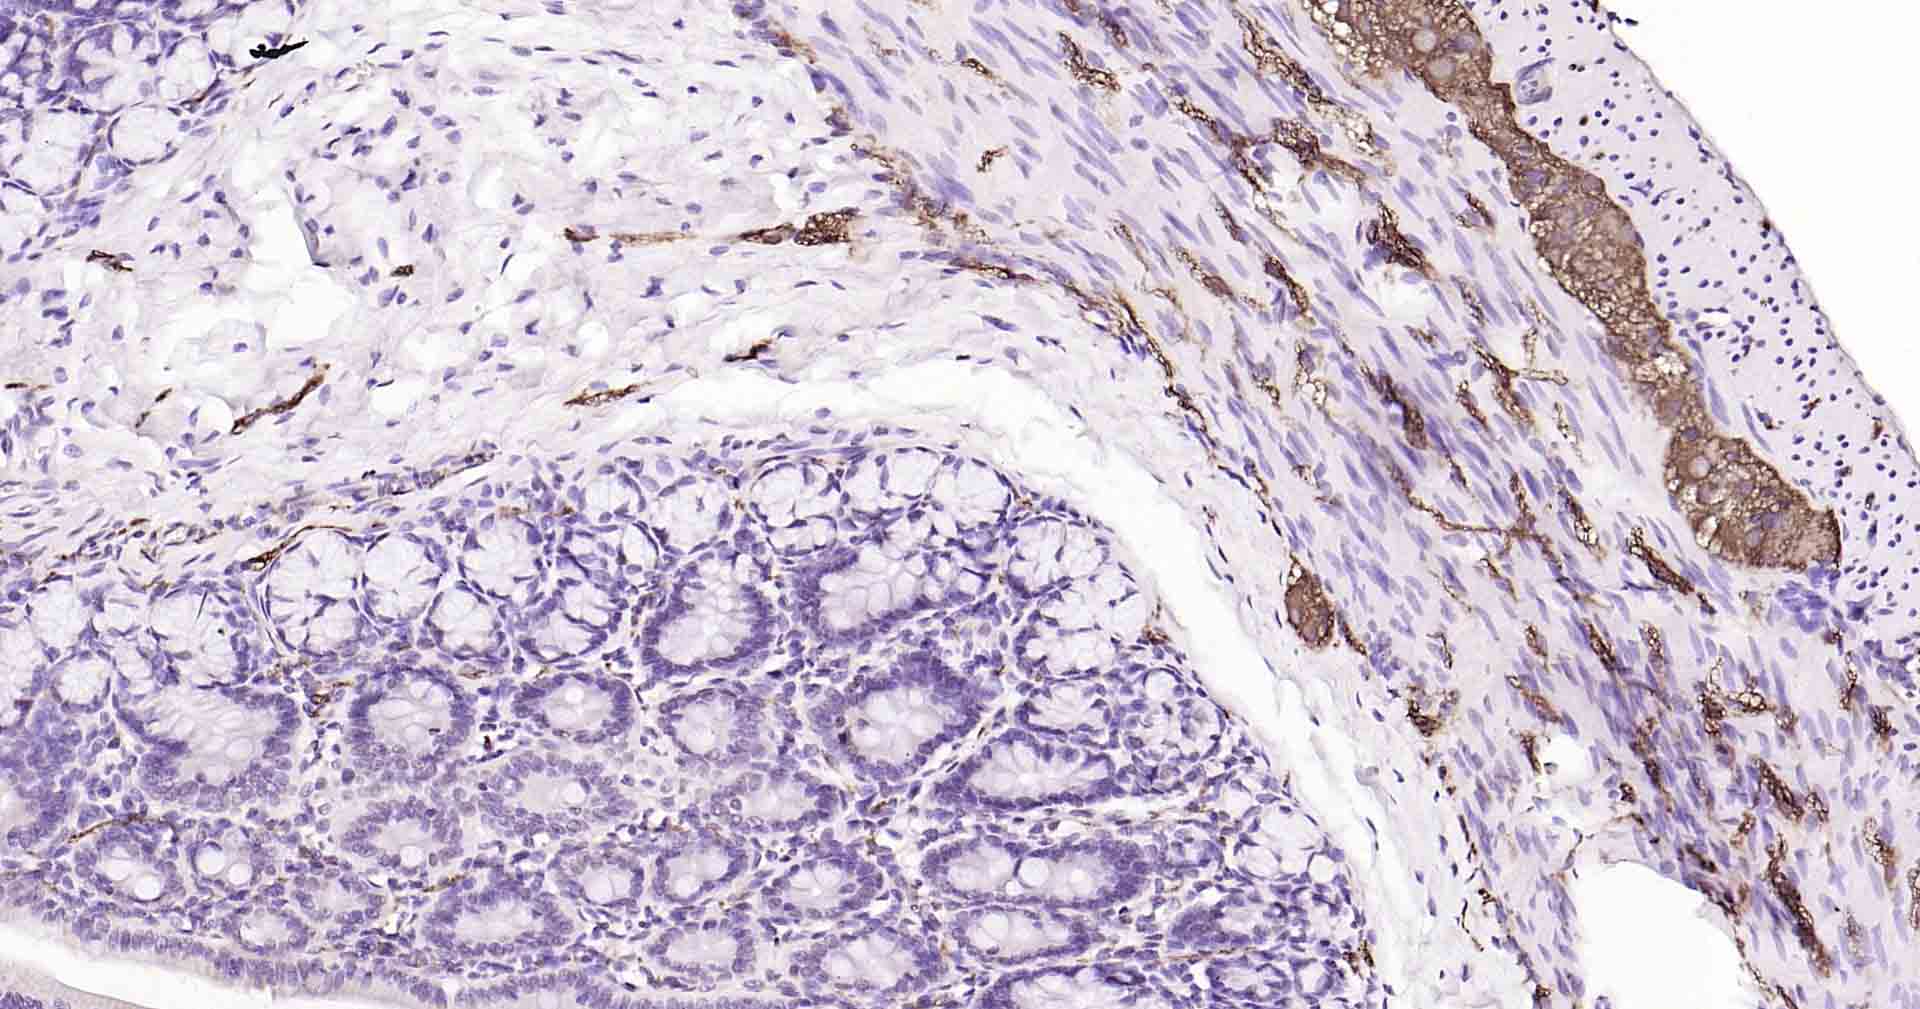

IHC-PHuman, Mouse, Rat1:50-200

IHC-FHuman, Mouse, Rat1:50-200

IFHuman, Mouse, Rat1:50-200